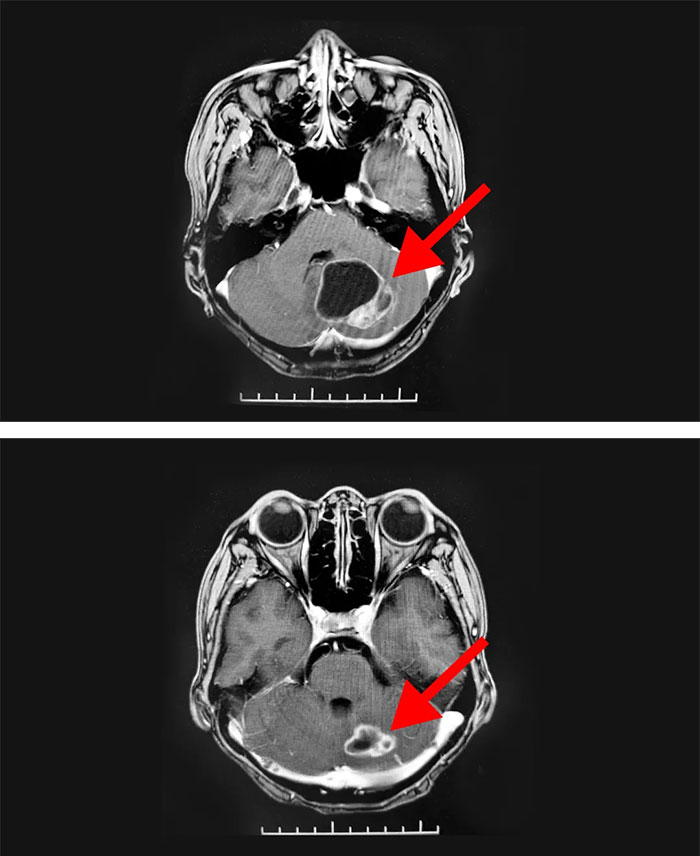

年近六旬的史女士(化名),11年前确诊乳腺癌并进行了手术切除。这些年来,她经过多次放、化疗治疗控制病情,但在2019年11月复查时,发现全身多发骨转移,并立即开展治疗。今年6月,她突然出现头晕等症状就医检查,经外院诊断,明确为左侧小脑半球转移瘤。

随后,患者慕名来到上海蓝十字脑科医院放疗科,通过放疗一个月后顺利出院。近期,患者回院复诊,影像学检查显示,病灶明显缩小,患者对治诊结果表示满意。临走时,她紧紧握住科室主任王晓东的手表达由衷感谢:“我是听朋友介绍说你们的放疗设备先进,医生团队专业。看来是来对了!”

▲ 经过放射治疗,病灶明显缩小